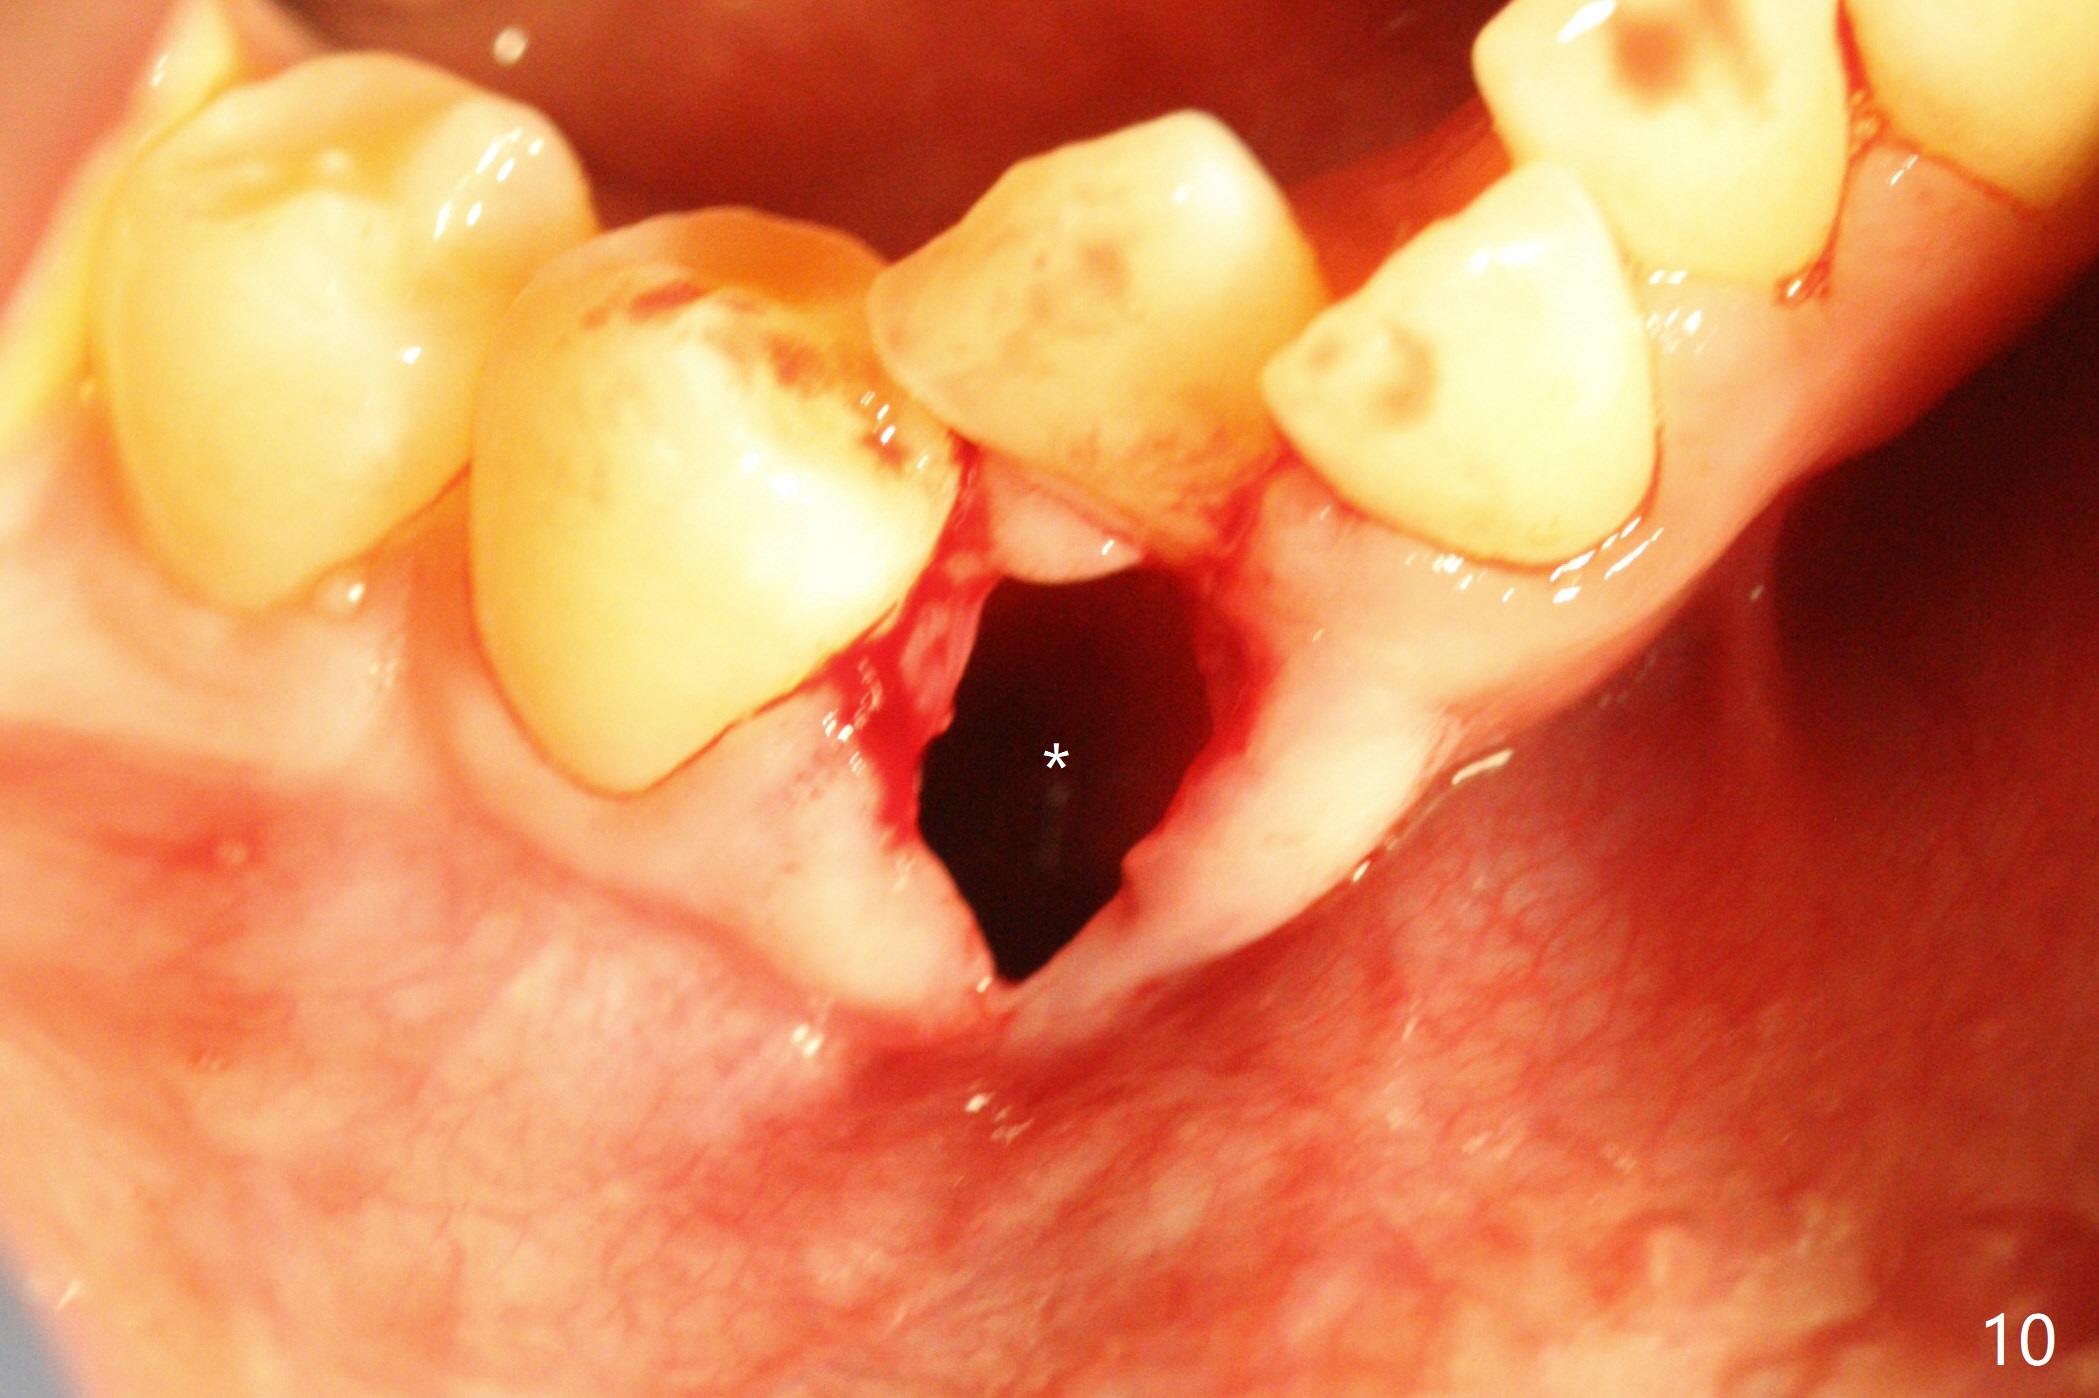

A 15-year-old man requests orthodontic treatment and agrees with extraction.  It appears that the maxilla is more protrusive than the mandible (Fig.1-4, 6,8).  The lower right canine has severe gingival recession (Fig.6,7,10).  Can we extract U4s and LR3 or 2 instead, considering relatively normal alignment in LL (Fig.8, occlusal view)?

In fact, extraction of LR3 is easier than the other three, because of its labial socket (Fig.10 * (loss of the labial plate), as compared to Fig.9).  Nevertheless, the root of LR3 is the longest (Fig.11).